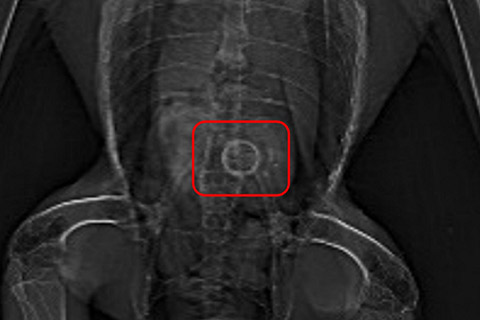

誤飲をしたトビ